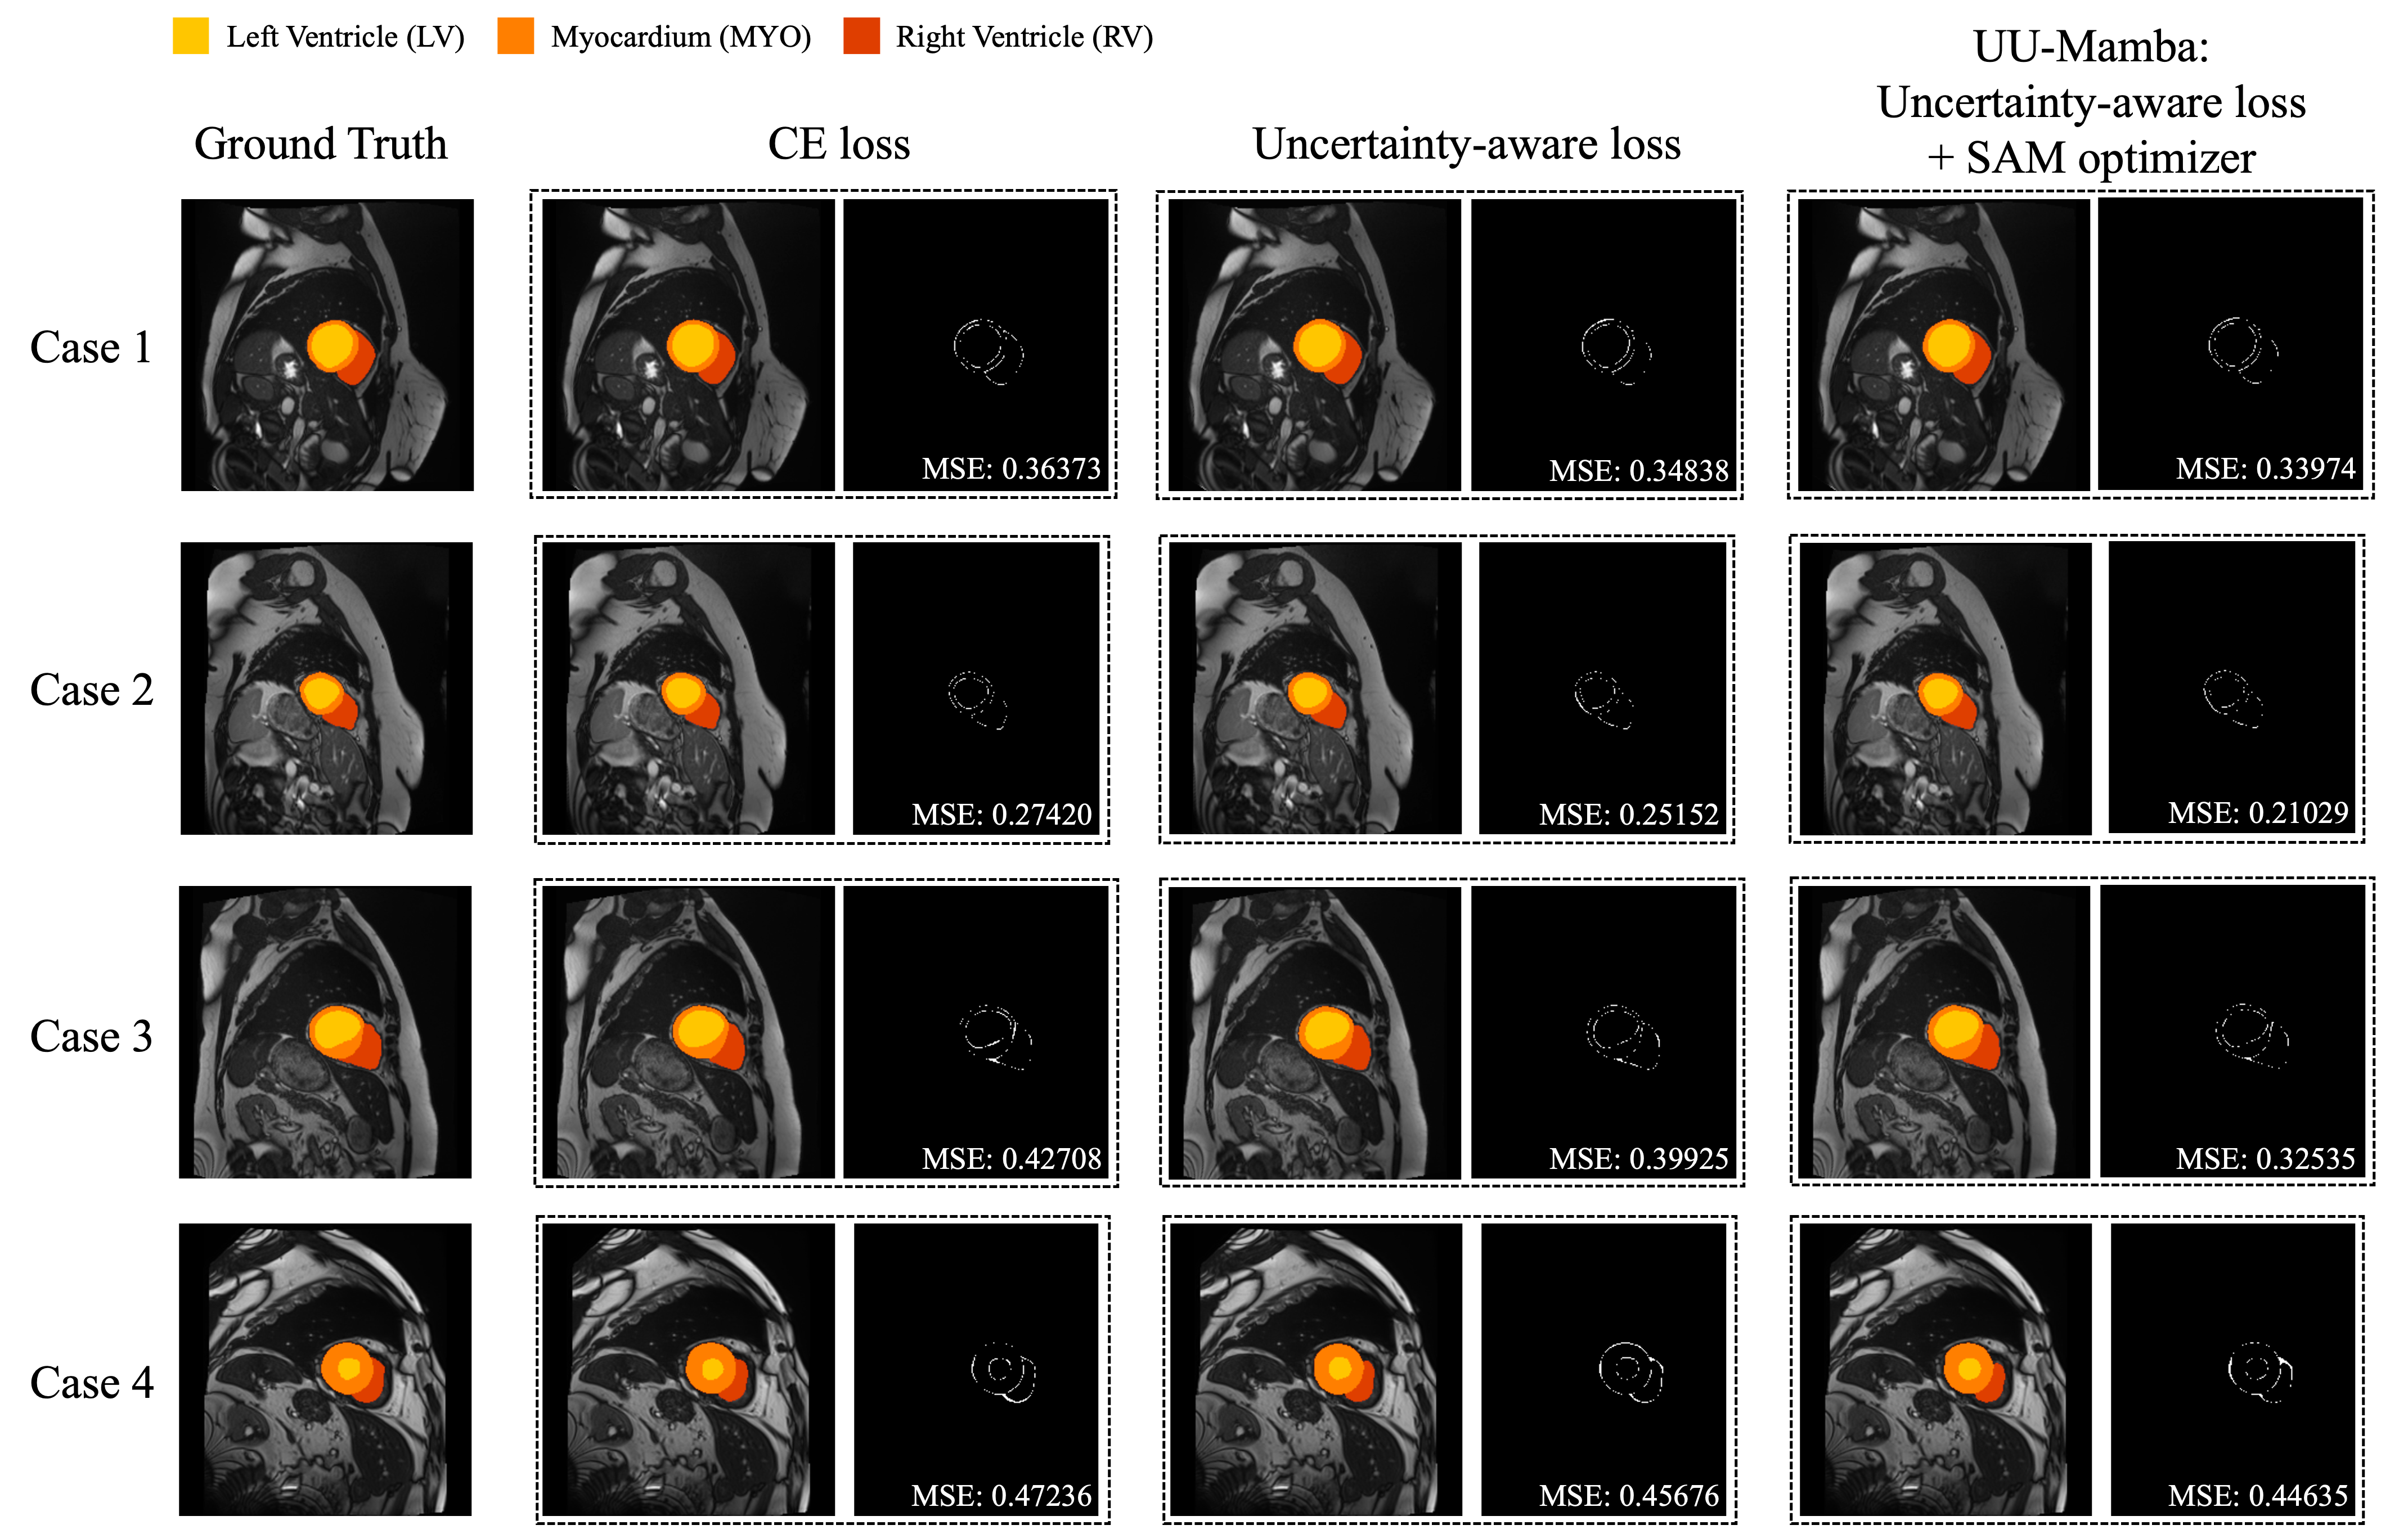

We conducted a quantitative evaluation of our UU-Mamba against the five other 3D heart area segmentation models on the ACDC dataset, using DSC as the evaluation metric. Fig. 3 shows the segmentation results for the methods in comparison on a few images from the ACDC dataset. Table II reports the DSC scores for each model at three heart regions: the right ventricle (RV), myocardium (Myo), and left ventricle (LV), as well as the average DSC scores of all regions. The best performing scores are marked in bold.

In Fig. 3, the MSE between the output segmentation and the ground truth is shown for each method, providing a visual comparison of the segmentation quality.